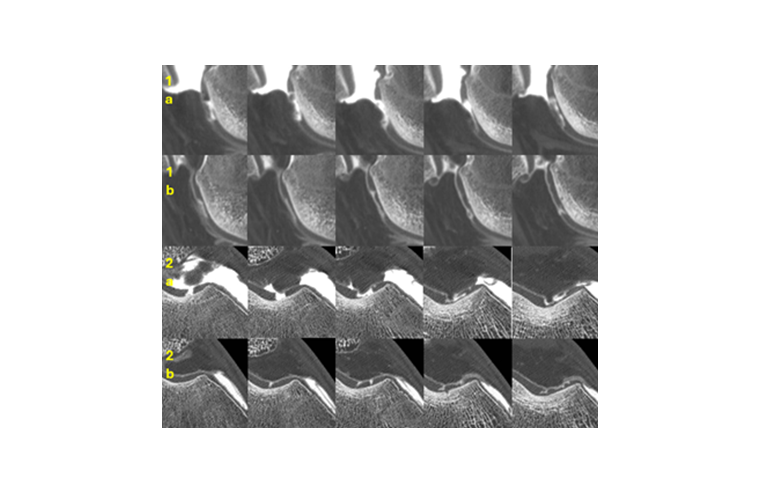

Beyond the protocol, our preliminary clinical experience supports the relevance of this treatment. To date, approximately twenty patients have been treated, including several elite athletes. We present here the case of a professional football player with a complete trochlear chondral lesion. Eight months after a combined autologous fat therapy + PRP injection, over 50% regression of the cartilage defect was observed on follow-up arthro-CT, along with a full return to professional-level football, completely asymptomatic.

The attached images (sagittal and axial CT series before and after treatment) illustrate this particularly striking clinical and radiological evolution.

Figure 1 : Response to a medial trochlear chondral lesion to autologous fat therapy on a 30 years old elite soccer player arthro-CT

• Sagittal series from medial to lateral, before (1a) and after (1b) autologous fat therapy

• Axial series from medial to lateral before (2a) and after (2b) autologous fat therapy